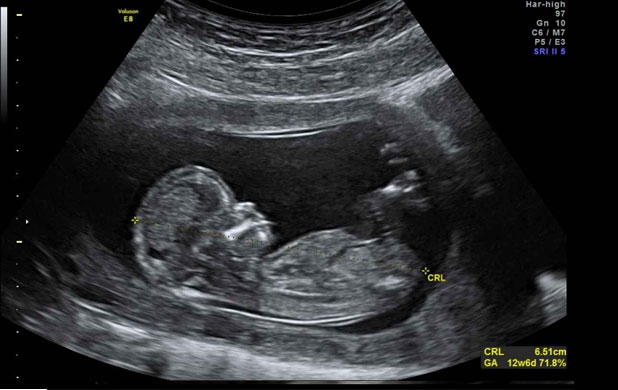

U medicini se ultrazvuk primjenjuje u dijagnostici

|